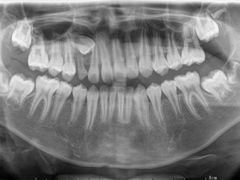

• 牙博士口腔品牌连锁(杨浦店)

• -牙博士口腔品牌连锁(杨浦店)